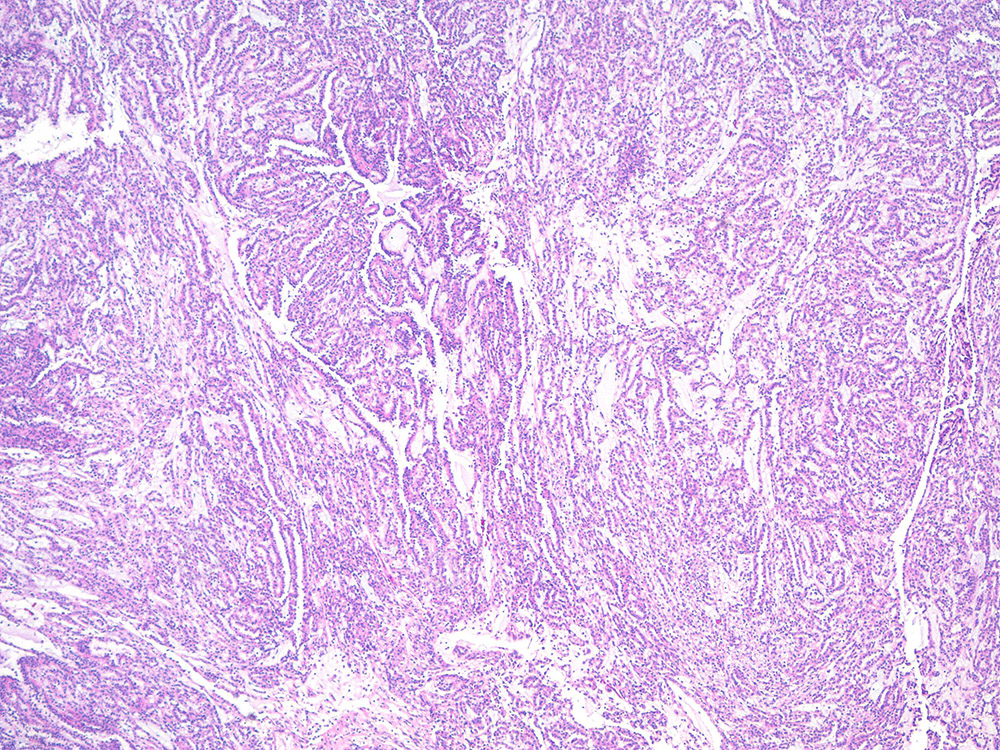

Classification of renal tumors

Case ID: 315